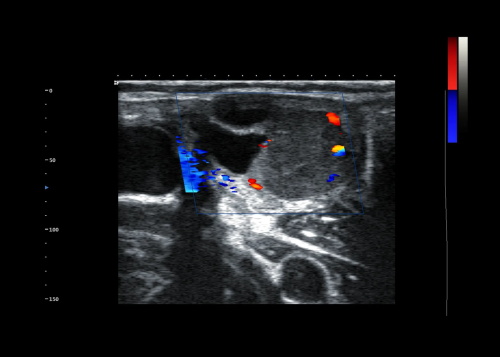

Color Doppler Transducers: Provides a visual representation of blood flow patterns.

Color Doppler: For visualizing blood flow.

4. Color Mapping

Boxianglai devices use sophisticated algorithms to translate Doppler data into color-coded images, representing flow direction and velocity.